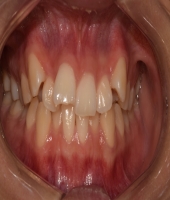

| ● 진료과목 : [치아교정] (교정)비발치 총생 치료

| ● 내용 : 심한 총생에서도 발치 없이 교정치료 |